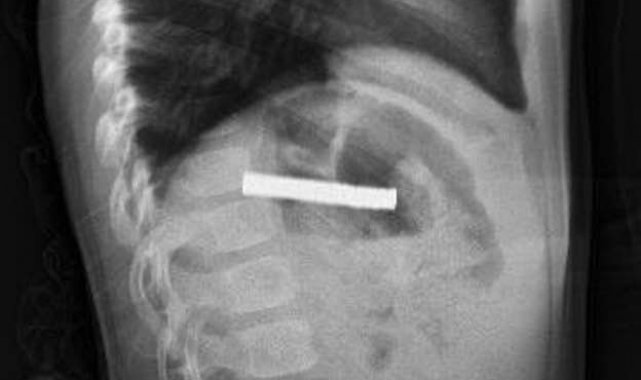

Edinilen bilgiye göre, Erzurum'da bir çocuk evde bulunan 19 tane mıknatısı yuttu. Çocuğun rahatsızlanması sonucu durumu öğrenen aile hastaneye başvurdu. Daha sonra çocuk Elazığ'a sevk edildi. Fırat Üniversitesi Çocuk Gastroenteroloji Hepatoloji ve Beslenme Bilim Dalı Başkanı Prof. Dr. Yaşar Doğan, çocuk hastanın yemek borusuna yapışmış 19 mıknatısı endoskopik yöntemle çıkardı.

Mıknatıslar uzun süre yemek borusunda takılı kaldığı için yemek borusu ve mide girişinde zedelenmeler olurken, çocuğun sağlık durumunun iyi olduğu ve taburcu edildiği öğrenildi.